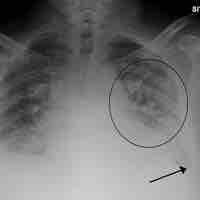

Dead space is a broken down or blocked region of the lung that produces a mismatch of air and blood in the lungs (V/Q mismatch).